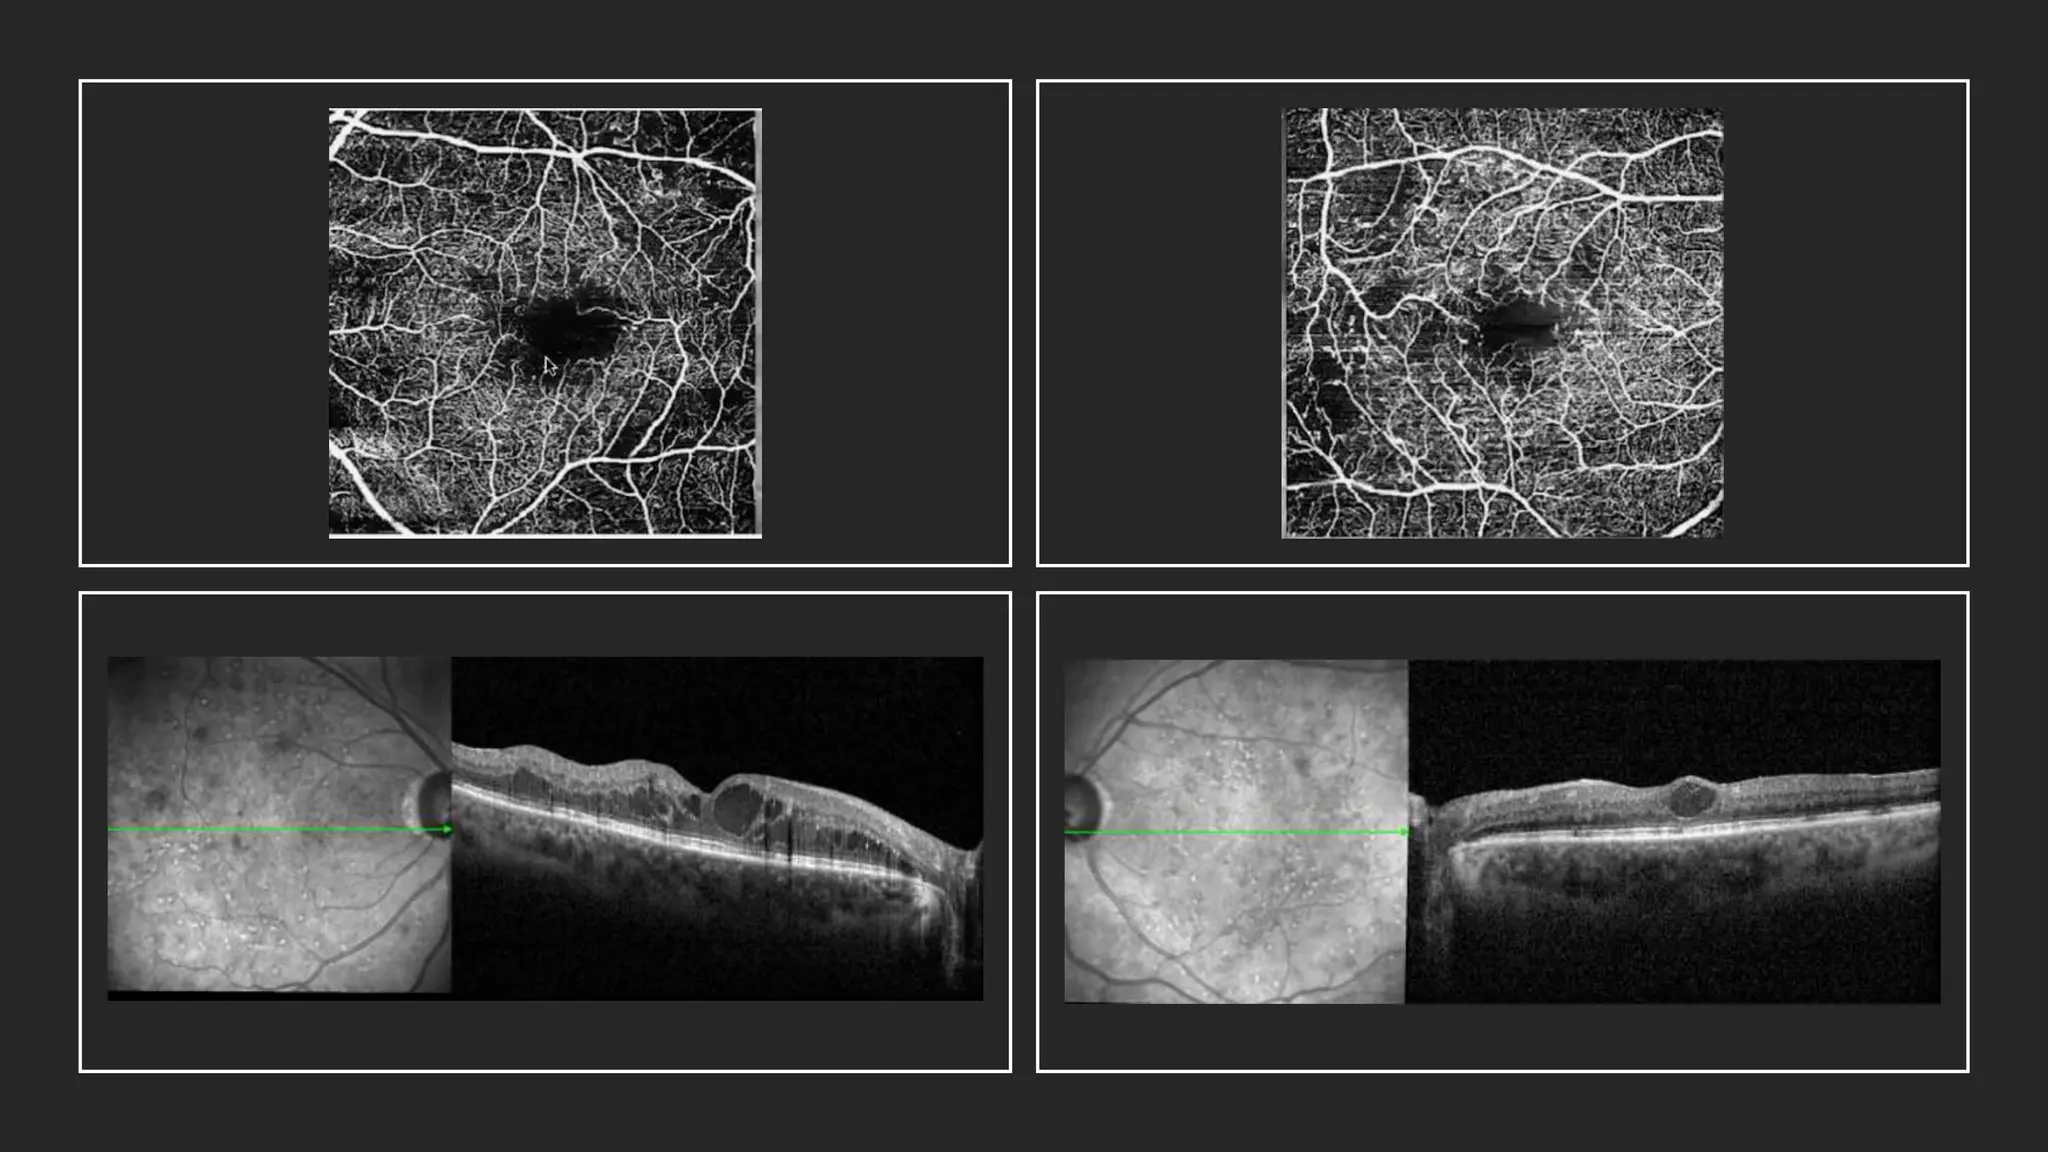

OCT/OCTA

Imaging

Microaneurysm:

• Hyperreflective contour & Continuous .. No

leakage

• Loss of continuity … leakage

• OCT delineate the capsular structure,

hyperreflective spots, and location of

microaneurysms

• Microaneurysms with the ring sign

were positively correlated with

exudation